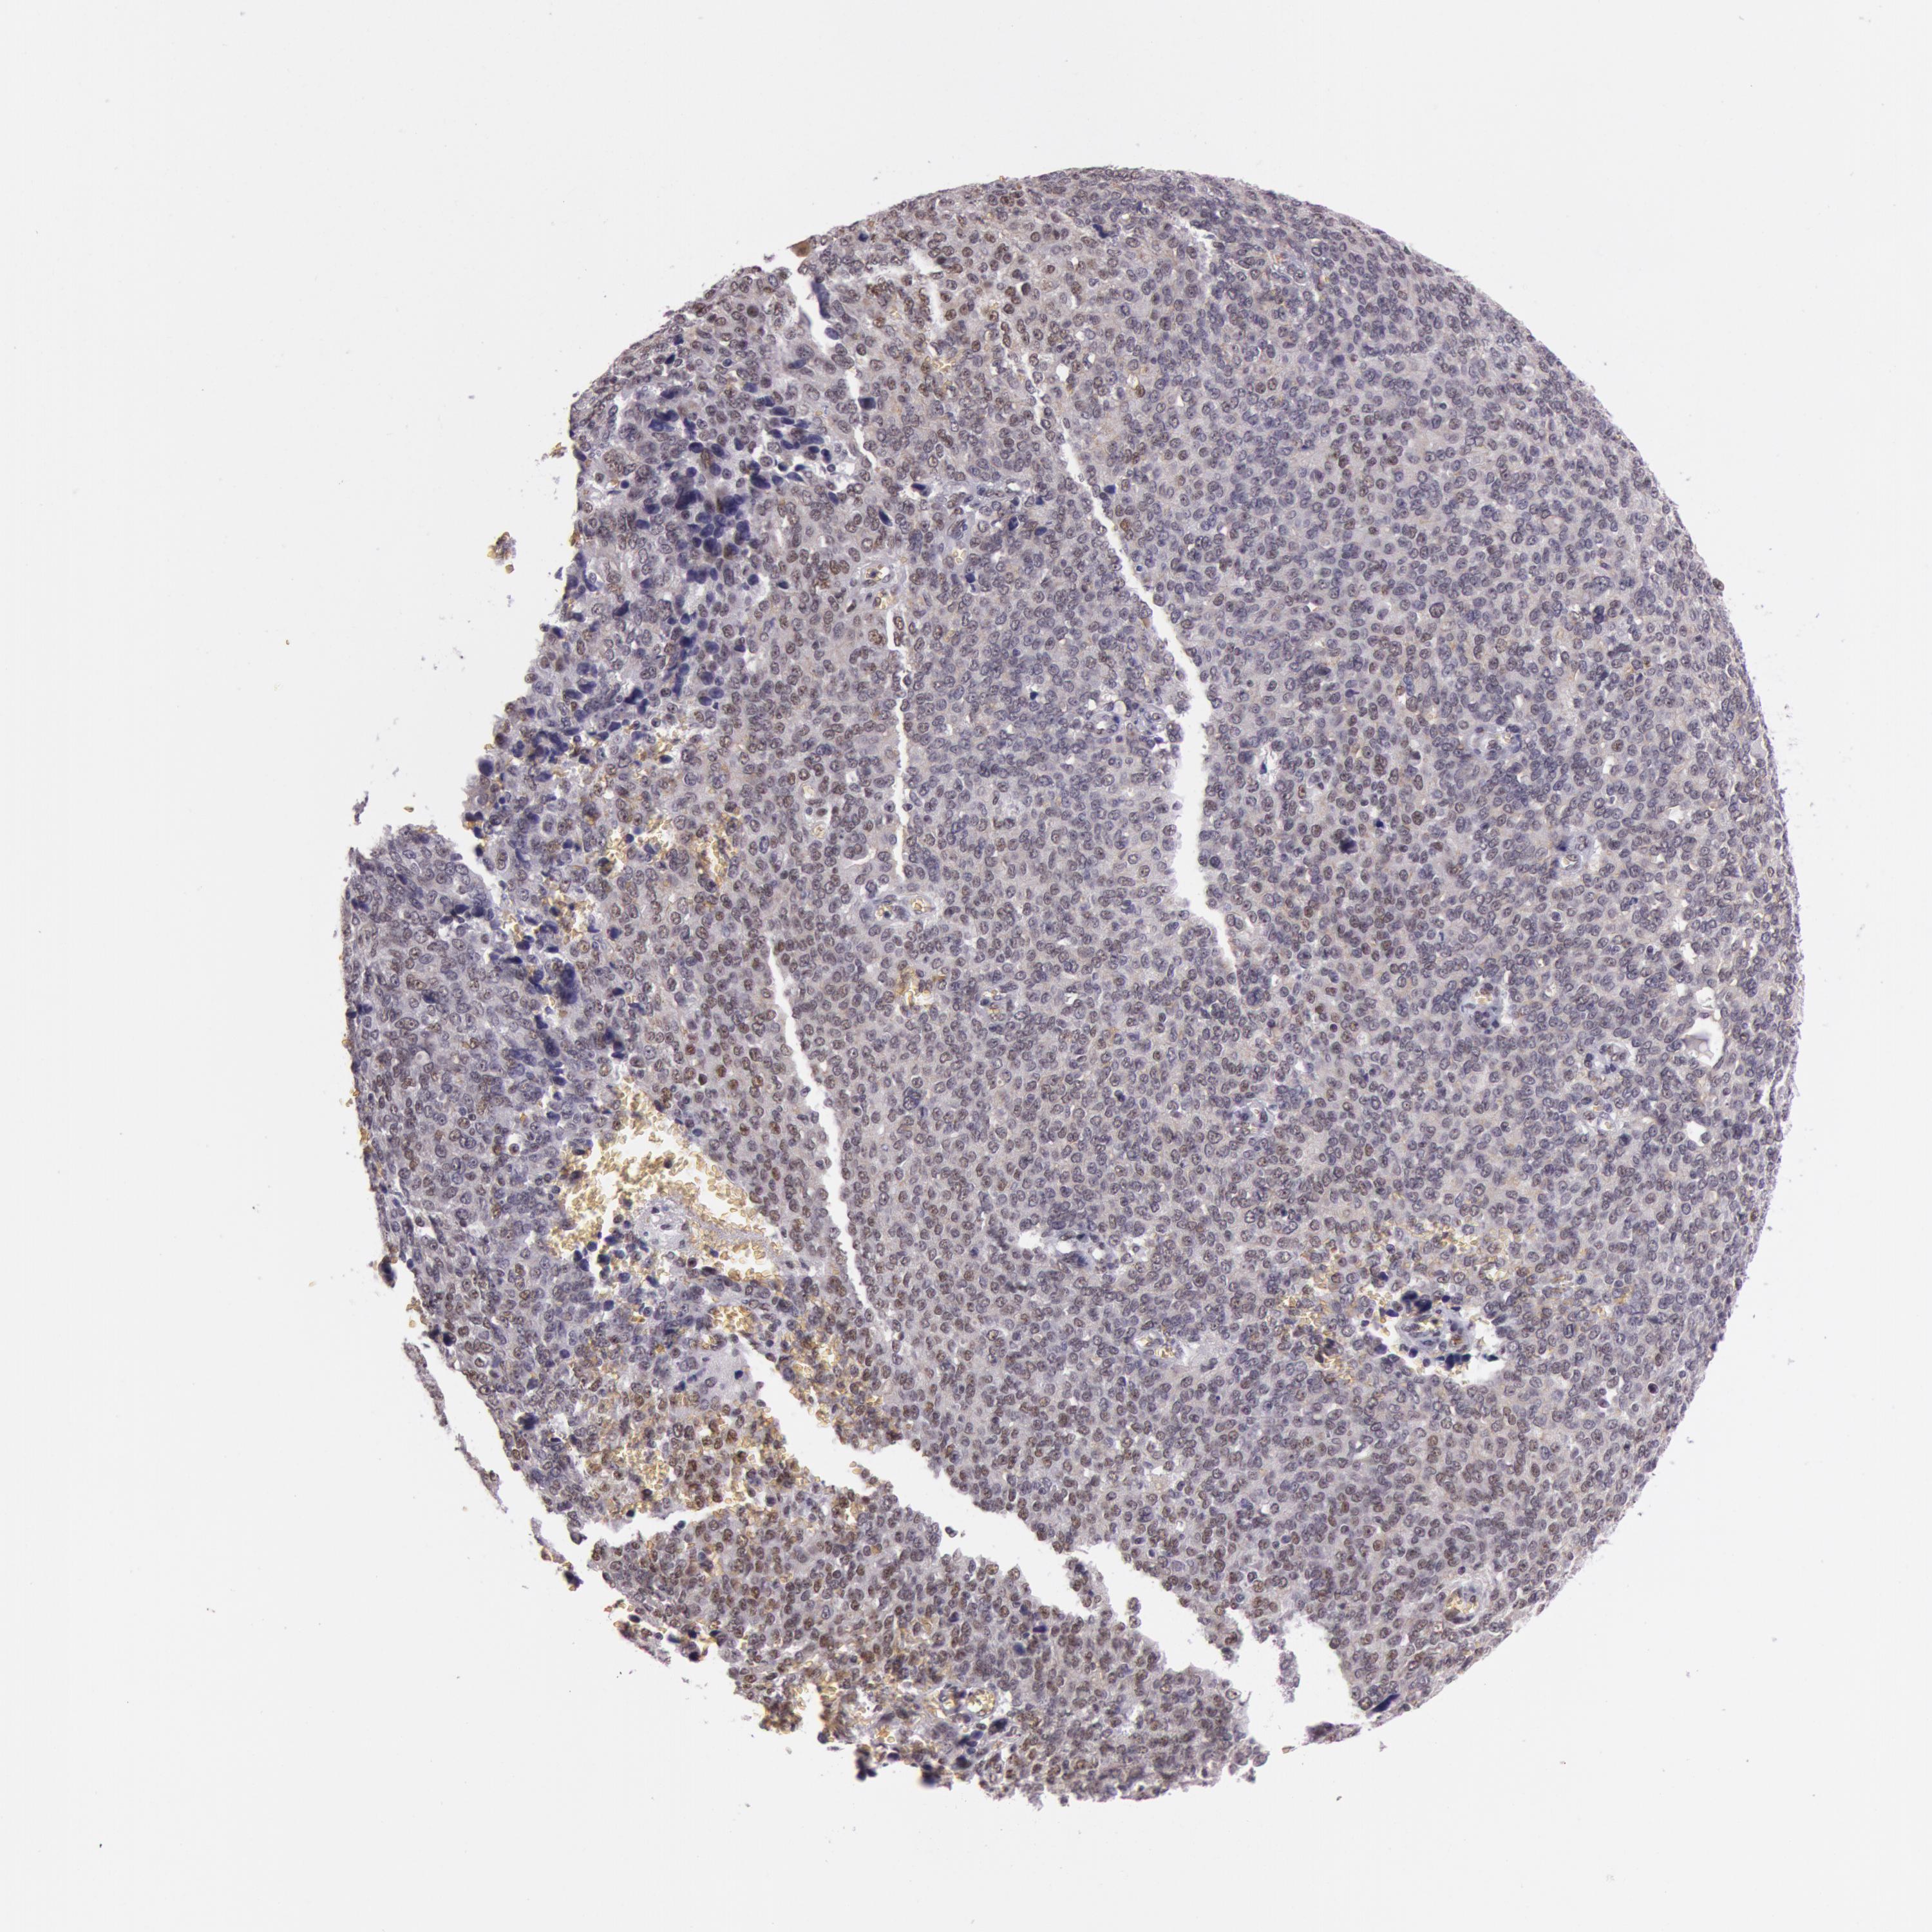

OVARIAN CANCER - Protein expressioni

A mouse-over function shows sample information and annotation data. Click on an image to view it in a full screen mode. Samples can be filtered based on level of antibody staining by selecting one or several of the following categories: high, medium, low and not detected. The assay and annotation is described here.

Note that samples used for immunohistochemistry by the Human Protein Atlas do not correspond to samples in the TCGA dataset.

Antibody stainingi

Antibody staining in the annotated cell types in the current human tissue is reported as not detected, low, medium, or high, based on conventional immunohistochemistry profiling in selected tissues. This score is based on the combination of the staining intensity and fraction of stained cells.

Each image is clickable and will lead to virtual microscopy that enables deeper exploration of all samples and also displays staining intensity scores, fraction scores and subcellular localization as well as patient and tissue information for each sample.

Antibody HPA001429

Antibody CAB003836

Antibody CAB080233

Carcinoma, endometroid

Cystadenocarcinoma, serous, NOS

Cystadenocarcinoma, mucinous, NOS